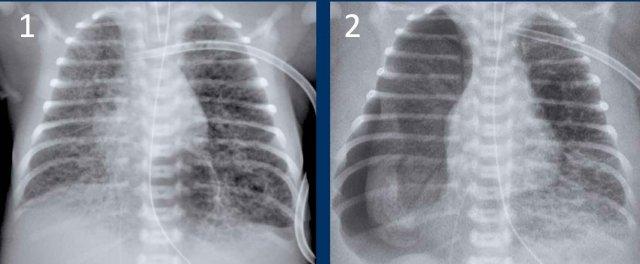

Hình ảnh

Trẻ sơ sinh một ngày tuổi, tuổi thai 27 tuần.

Mờ dạng hạt cả hai phổi.

Mạch máu và bóng tim được hiển thị rõ ràng.

Conclusion: RDS grade 1.

Đường truyền catheter trung tâm qua đường ngoại vi (PICC) bị cuộn trong tâm nhĩ phải. Đường PICC cần được rút lui đến mức tĩnh mạch chủ trên và tâm nhĩ phải.

One day old neonate, 29

weeks of gestational age.

Image

- Hyperinflation due to CPAP.

- Granular opacification of

both lungs with air bronchograms. - NG tube in good position.

- Vessels and cardiac

silhouette are harder to distinguish.

Conclusion: RDS grade 2.

One day old neonate, 26 weeks of gestational age.

- Granular opacification of both lungs.

- Vessels and cardiac silhouette are hard to distinguish.

- Umbilical venous line properly positioned.

- Vị trí đặt catheter động mạch rốn quá sâu, cần rút lại đến mức T6.

- NG tube in situ.

Conclusion: RDS grade 3.

One week old neonate, born at 27 weeks of gestational age.

- Vị trí ống nội khí quản quá sâu, cần được điều chỉnh lại về giữa khí quản.

- Diffuse granular opacification of both lungs.

- Air bronchograms.

- Các mạch máu phổi không còn nhận ra được nữa, nhưng bóng tim vẫn còn có thể nhận ra được.

- Opacification of the left lower lobe caused by atelectasis.

Không phân loại vì trẻ sơ sinh này đang được thở máy.